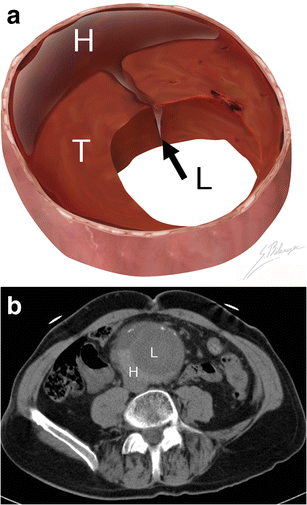

Hyperattenuating crescent sign. a Illustration demonstrates blood (black arrow) dissecting into a mural thrombus (T) from the aortic lumen (L). The resulting intramural haematoma (H) is crescent shaped. b Axial unenhanced CT of a 63-year-old man presenting with abdominal pain and a pulsating mass. A crescent (H) of higher attenuation than the aortic lumen (L) can be seen